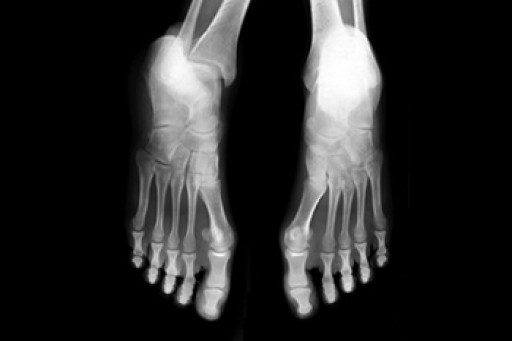

Broken Foot Causes, Symptoms, and Treatment

A broken foot is caused by one of the bones in the foot typically breaking when bended, crushed, or stretched beyond its natural capabilities. Usually the location of the fracture indicates how the break occurred, whether it was through an object, fall, or any other type of injury.

Common Symptoms of Broken Feet:

- Bruising

- Pain

- Redness

- Swelling

- Blue in color

- Numbness

- Cold

- Misshapen

- Cuts

- Deformities

Those that suspect they have a broken foot shoot seek urgent medical attention where a medical professional could diagnose the severity.

Treatment for broken bones varies depending on the cause, severity and location. Some will require the use of splints, casts or crutches while others could even involve surgery to repair the broken bones. Personal care includes the use of ice and keeping the foot stabilized and elevated.